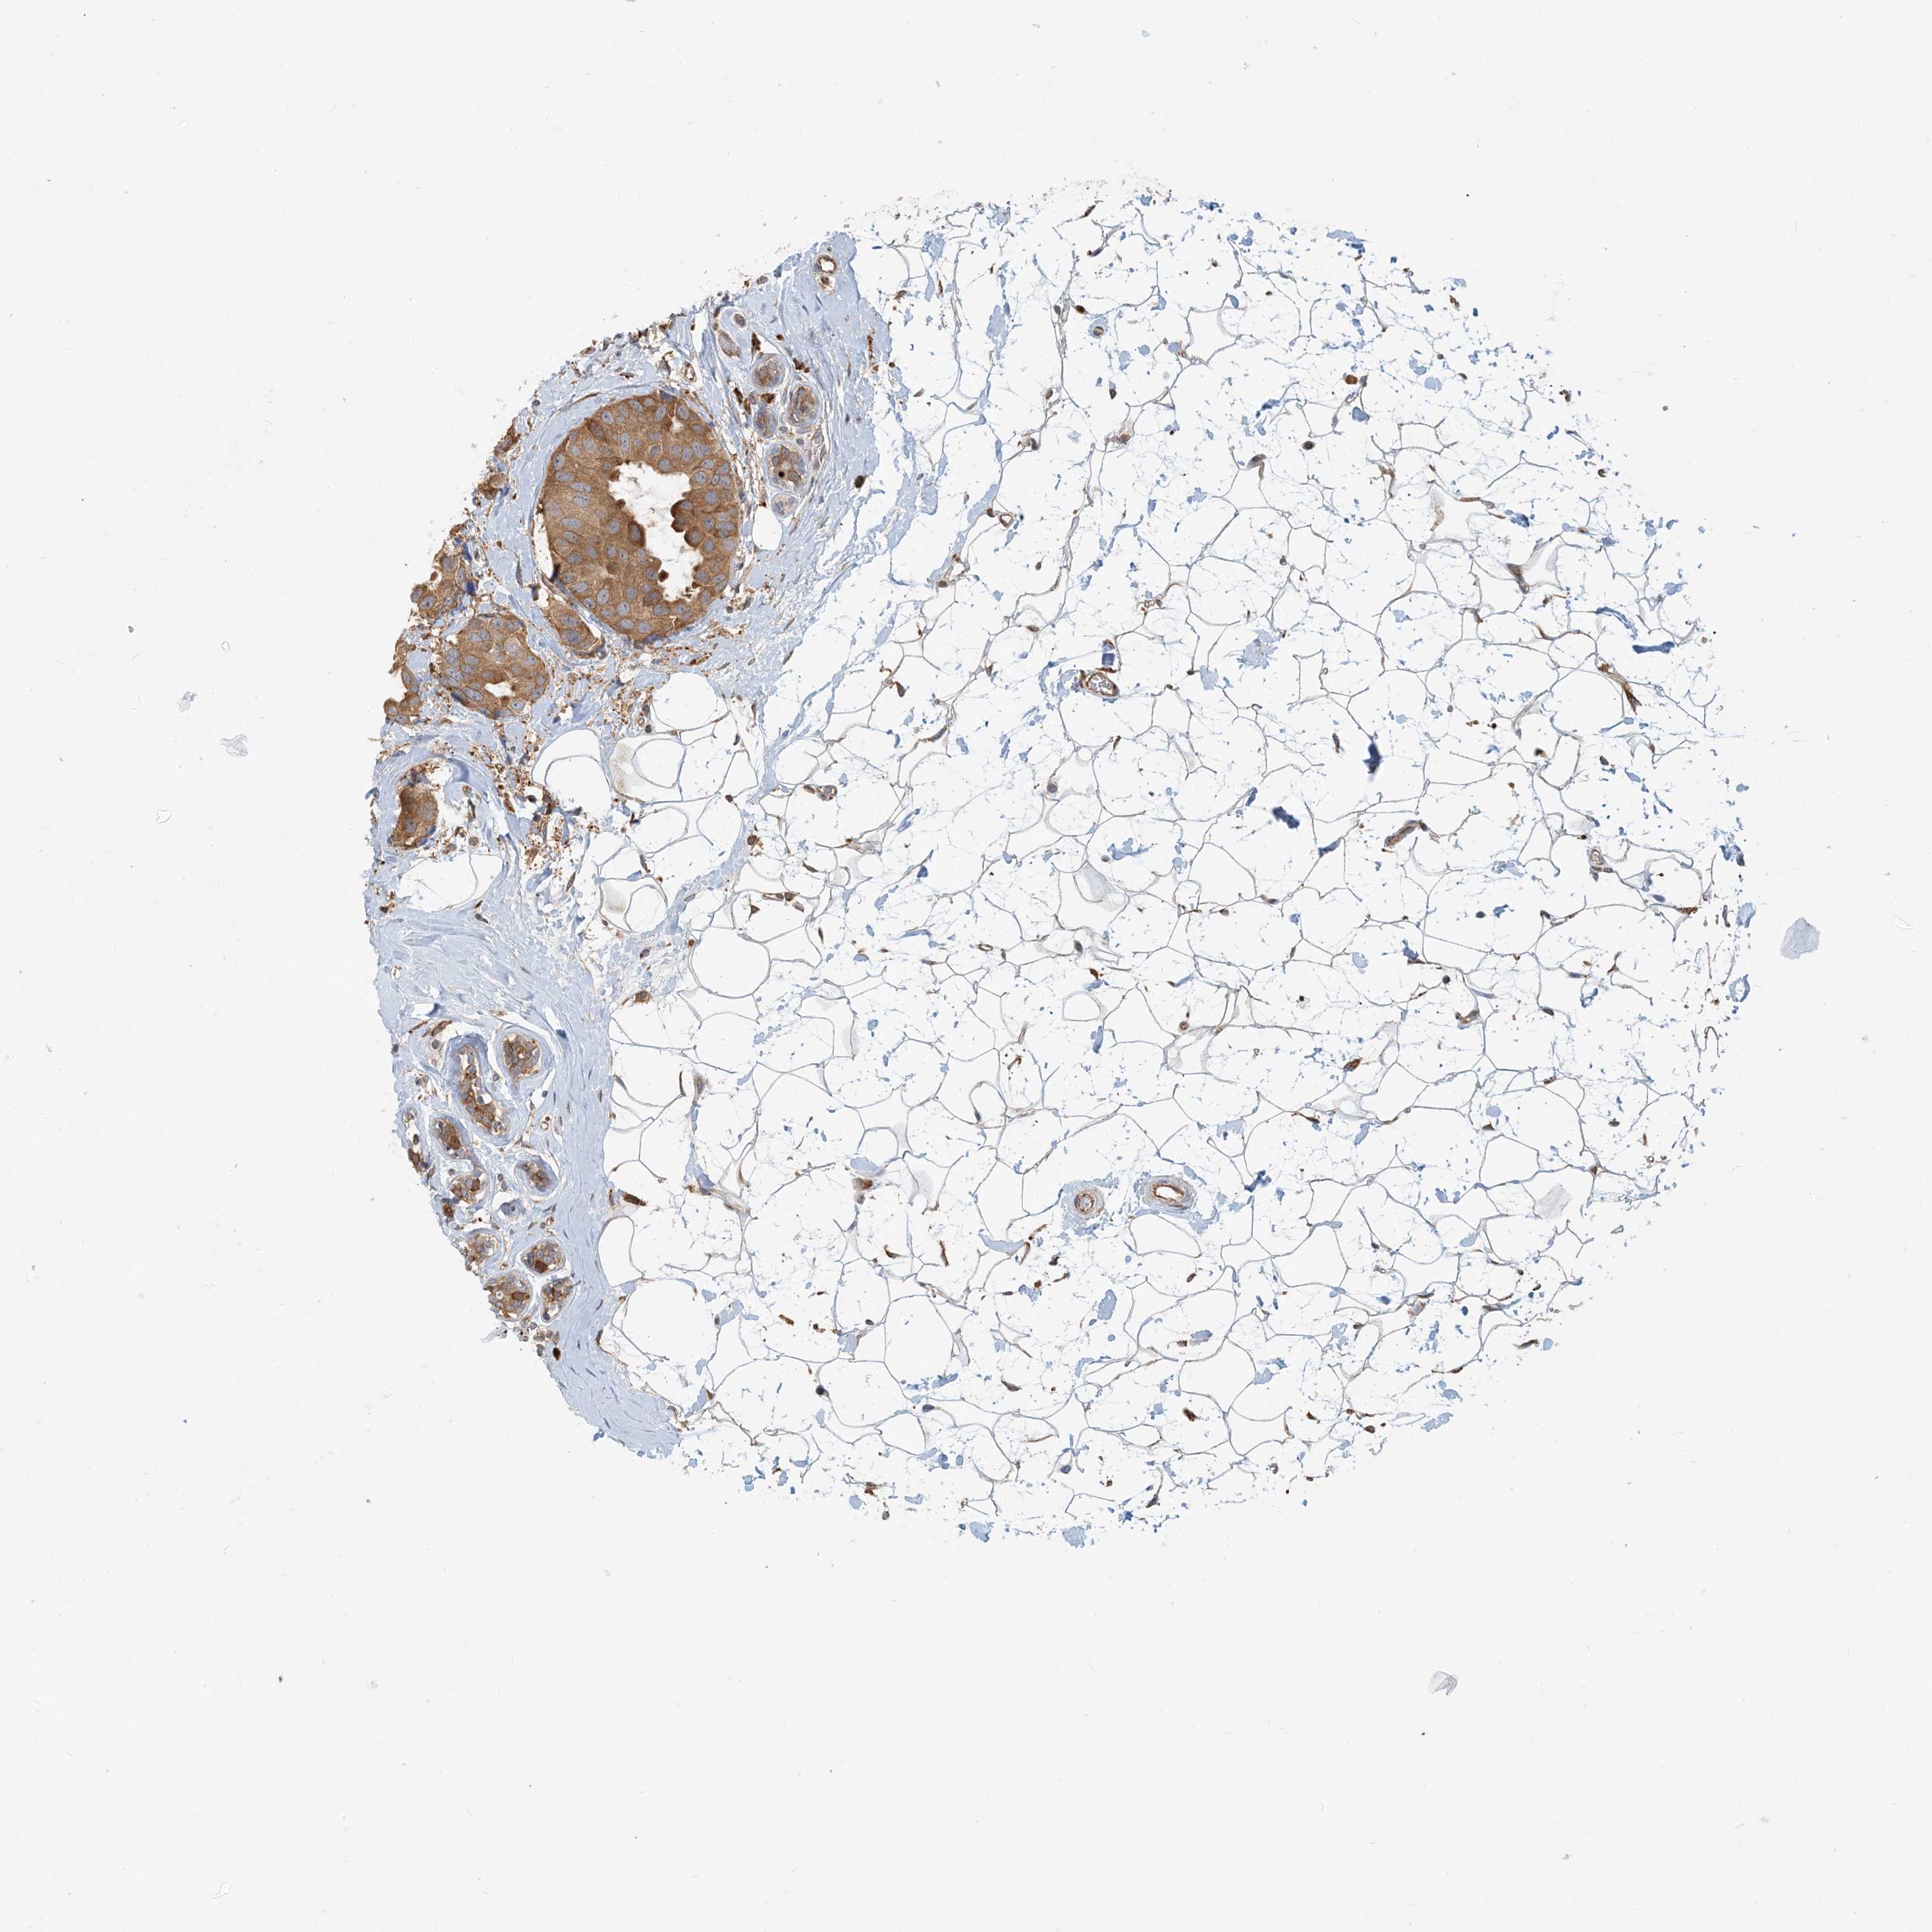

BRCA TCGA BRCA VALIDATION PROTEIN EXPRESSION

ANTIBODIES

AND

VALIDATION